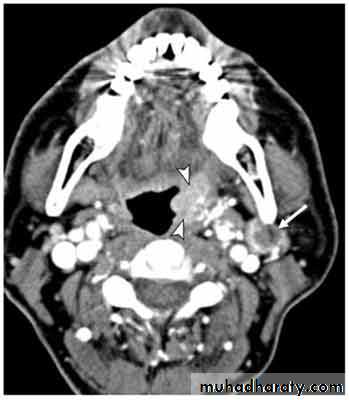

3- CTS and MRI : site and extent of the tumor

4- angiography: shows a vascular blush in the nasopharynx and is useful to determine the feeding vessel

Site of origin: sphenopalatine foramen present on the lateral wall of the nasal cavity. It then extends into the nasal cavity, paranasal sinuses, orbit and even intracranially.